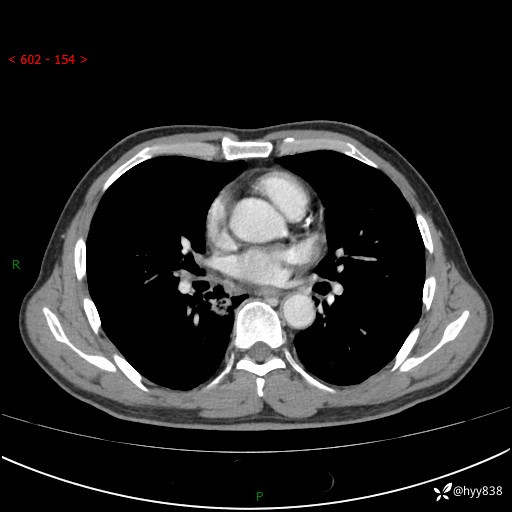

69岁/男,发现肺部病变6天。该有的征象都有,肉芽肿 VS 肿瘤,一念之间---(有结果)

主诉:发现肺部病变6天。

现病史:患者6天前于我院泌尿外科住院,住院期间行胸部CT检查,提示“肺部病变”,患者无畏寒、发热、盗汗、咳嗽、咳痰、咯血、胸痛、呼吸困难,无反酸、腹痛、腹泻、头痛、头晕等不适。未予特殊处理,现为进一步诊治,门诊以“肺肿物”收入我科。 患者本次起病以来,精神食欲尚可,大小便正常,体力及体重无明显变化。

胸部CT平扫+增强